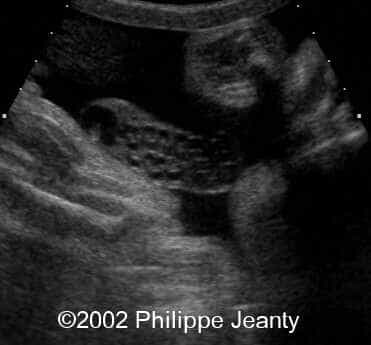

Ultrasound appearance

A transverse section of the umbilical cord shows two vessels. Examination of umbilical blood flow with color Doppler may facilitate diagnosis. However, by far the easiest way to assess the number of arteries, is by identifying the intra-abdominal portion of the umbilical artery along side the bladder with color Doppler17,18.